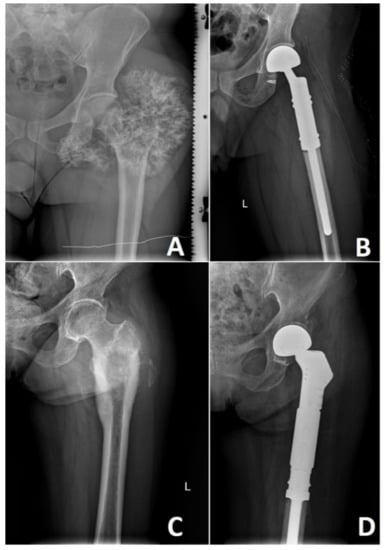

5. Surgical Treatment of Chondrosarcoma

- Bingold, A.C.; Percy, A.J. Prosthetic replacement of a chondrosarcoma of the upper end of the femur: A 43-year follow-up. J. Bone Joint Surg. Br. 1996, 78, 663–664. [Google Scholar] [CrossRef] [PubMed][Green Version]

- Bingold, A.C. Prosthetic replacement of a chondrosarcoma of the upper end of the femur. Eighteen-year follow-up. J. Bone Joint Surg. Br. 1972, 54, 139–142. [Google Scholar] [CrossRef] [PubMed]